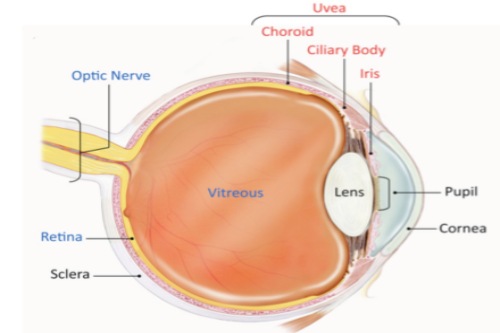

术前,患者需接受超全眼科检查,包括视力测试、眼底检查和OCT扫描,以评估病情并制定手术方案。

手术通常在局部或全身麻醉下进行,医生会在巩膜处制作微小切口,插入显微手术器械。

剥除后,详细检查视网膜表面是否有残留膜,并清理干净。然后,向眼内注入平衡盐溶液维持眼球形状,闭合切口。